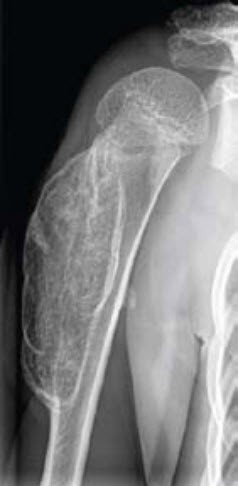

Abb. 1 zeigt eine grosse, breitbasige Exostose am proximalen Humerus. Tatsächlich ist das Ausmass der Exostose viel grösser, da die bedeckende Knorpelkappe nativradiologisch nicht dargestellt wird.